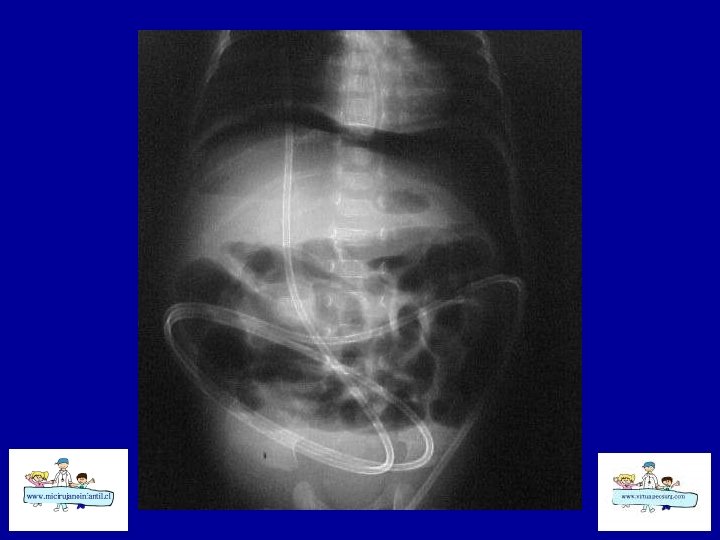

ECN-RADIOLOGÍA SIMPLE • • Distensión de asas Pneumatosis intestinal Asa fija (centinela) Gas Porta Edema de pared Ascitis Aire libre

ECN- Indicaciones de cirugía • Absoluta: Perforación intestinal • Relativas: Deterioro estado general, Masa palpable? , celulitis de pared, Gas Porta? , obstrucción intestinal, Paracentesis alterada, Asa centinela en Rx abdomen simple. • 25 a 30 % de ECN requieren cirugía. • 19 % en los > 1500 gr y 41 % en los < 1500 gr.

ECN-TRATAMIENTO • Quirúrgico: Laparotomías amplias • Drenaje peritoneal • Aseo abdominal y resección de asas necróticas • Ostomía vs Cierre primario • Second Loock